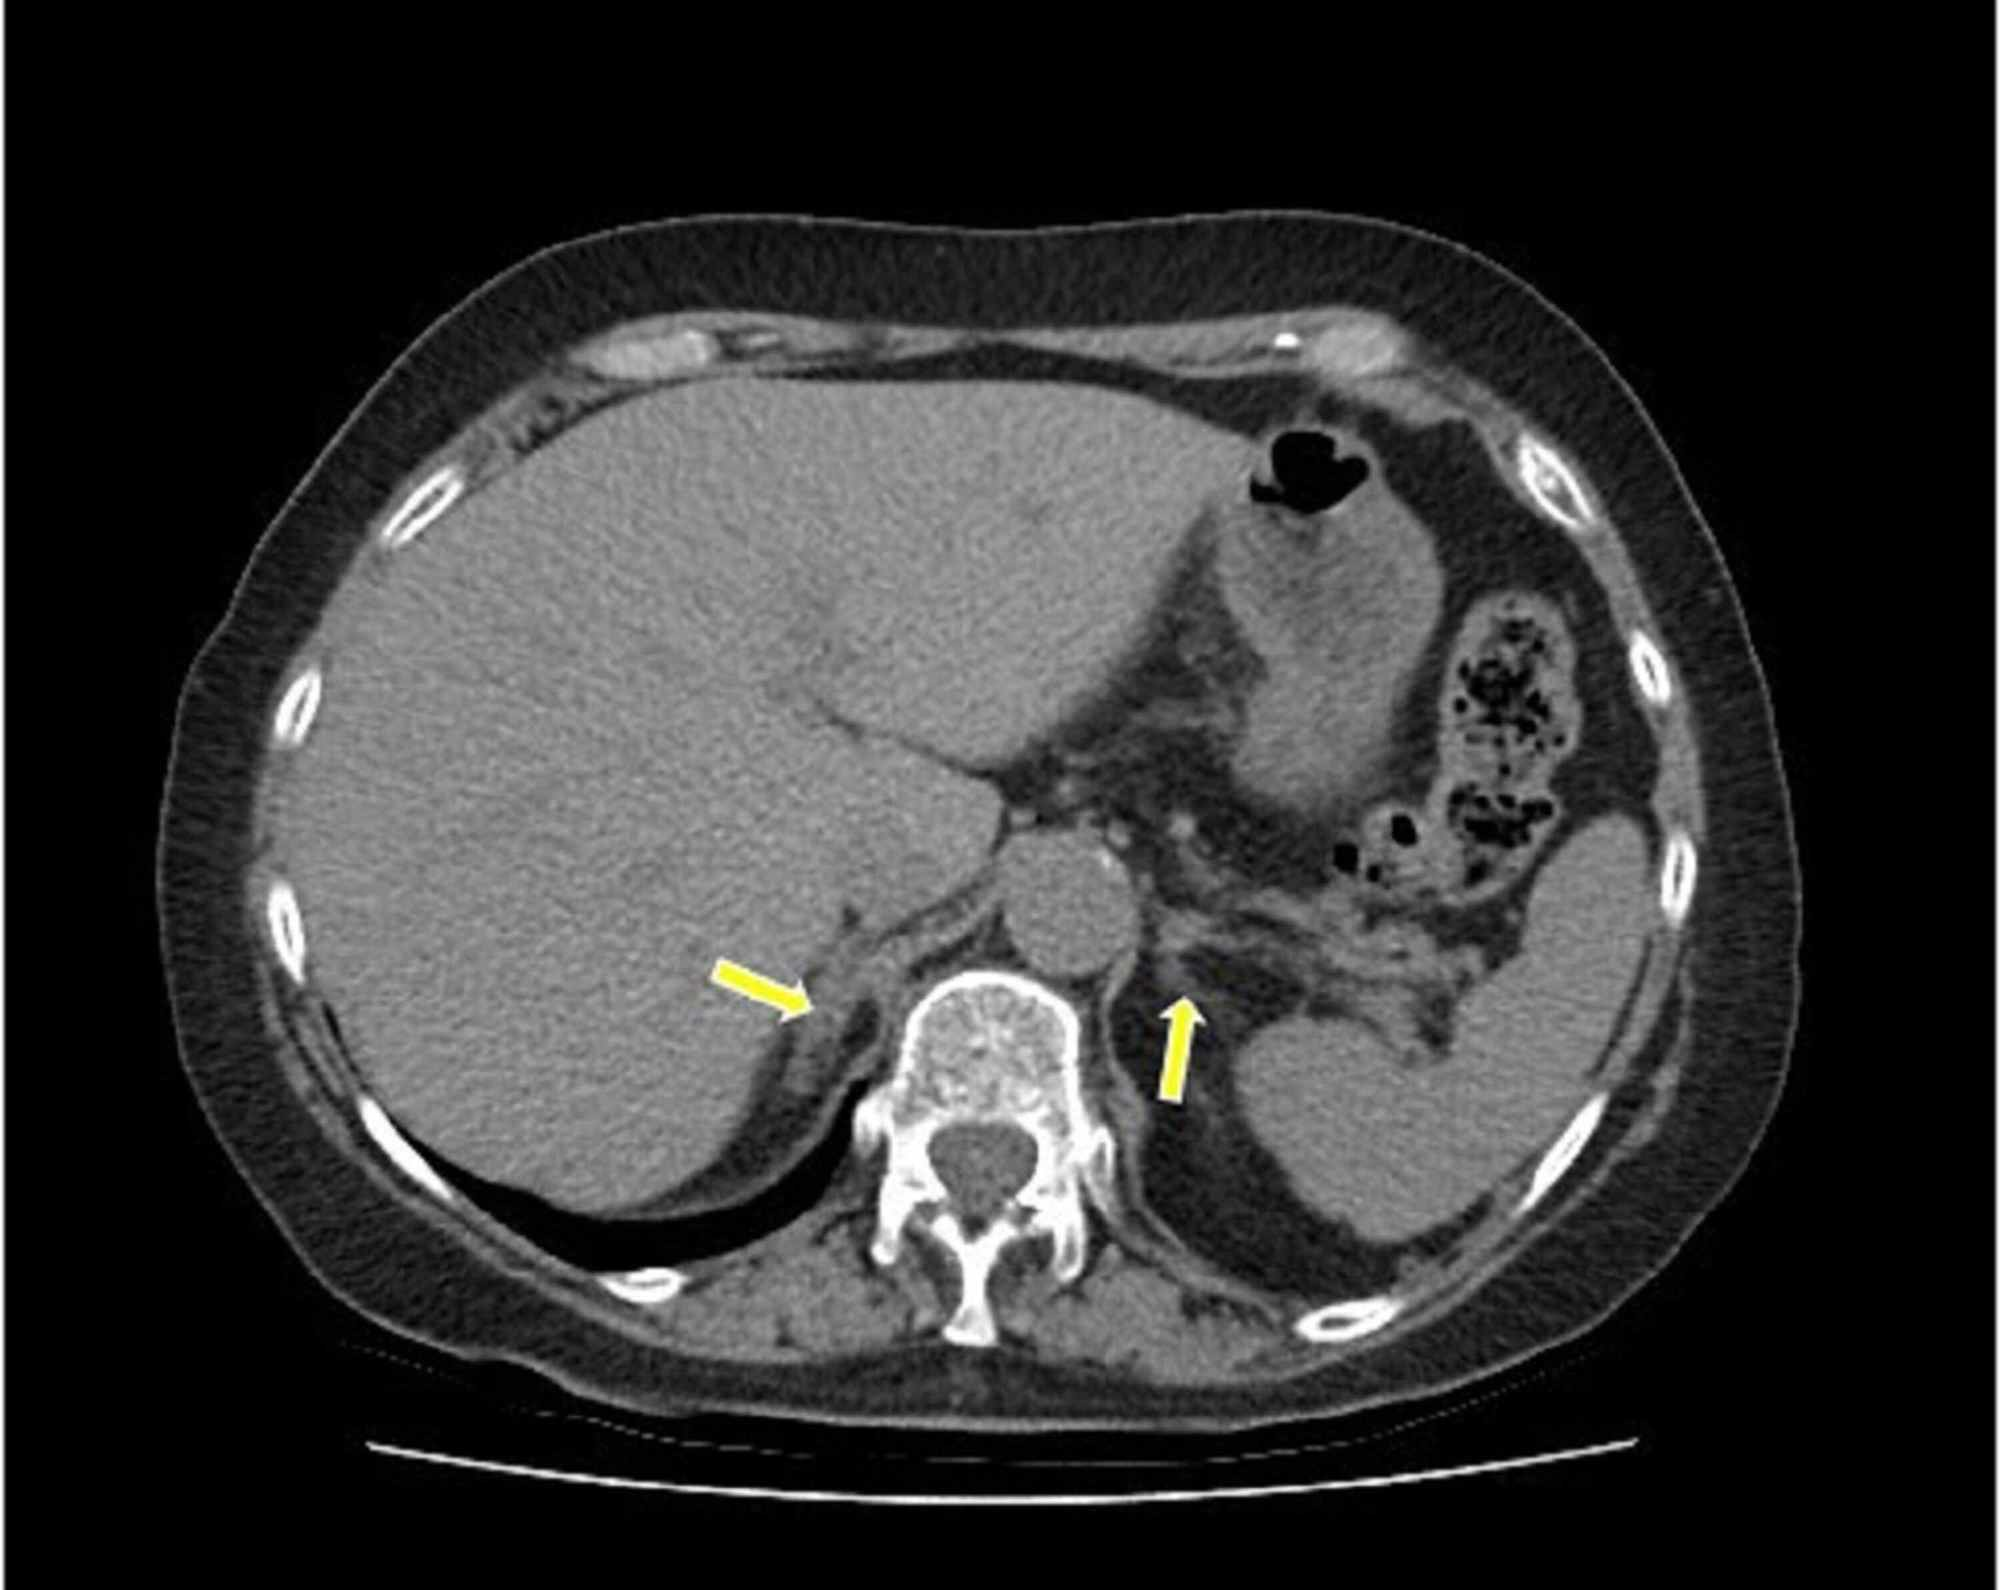

CT scan confirms bilateral adrenal hemorrhage. Adrenal congestion with What Causes Adrenal Gland Bleeding It is perceived as an uncommon clinical entity that. Adrenal hemorrhage, albeit rare, is potentially fatal. Adrenal hemorrhage refers to bleeding within the capsule of 1 or both adrenal glands. This is a rare autoimmune disease that causes your. Adrenal hemorrhage is an uncommon disorder characterized by bleeding into the suprarenal. Addison’s disease (primary adrenal insufficiency): 7,8 because of a. What Causes Adrenal Gland Bleeding.

From www.researchgate.net

From www.cureus.com